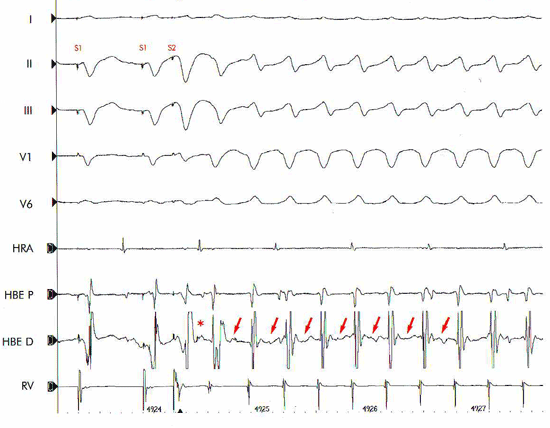

Hình 14: Kích thích thất sớm dần xác định thời gian trơ hiệu quả cơ thất. S1S2: 220 ms (trái) vẫn còn gây sóng khử cực thất; S1S2: 200 ms (phải) không còn gây sóng khử cực thất. Như vậy thời gian trơ hiệu quả cơ thất là 200 ms.

Hình 15: Kích thích thất sớm dần gây cơn tim nhanh thất